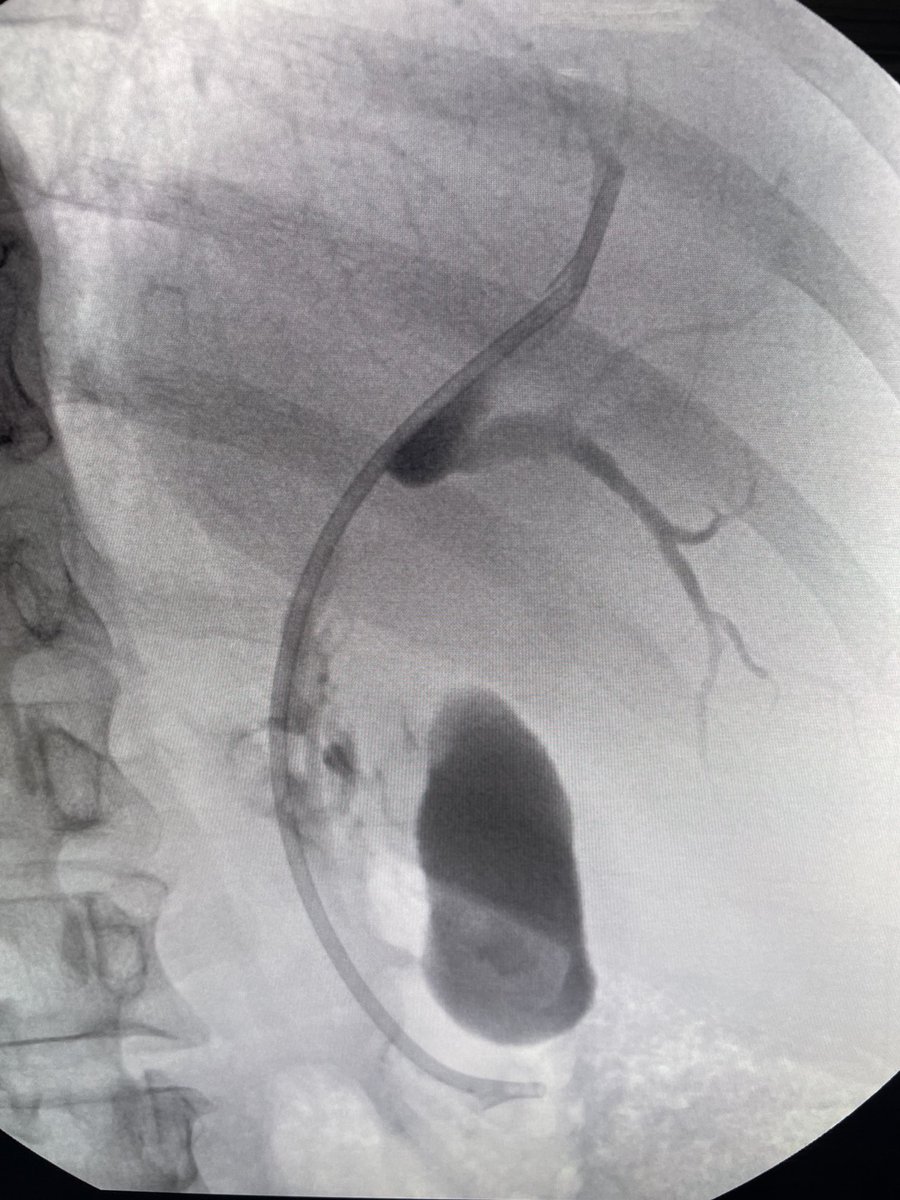

Cholangiocarcinoma. Entire left lobe replaced by mass. Tight hilar stricture. Right side stented to good effect. #gitwitter #surgery Prof John Leeds Neal Mehta Scot Michael Lewey Rahul Karna, MD